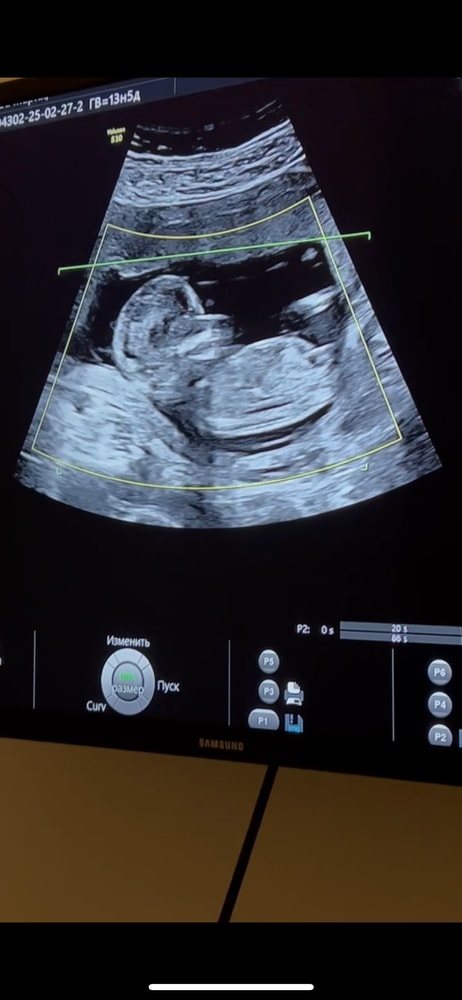

Анастасия, шнобель виден был уже)) Изображение